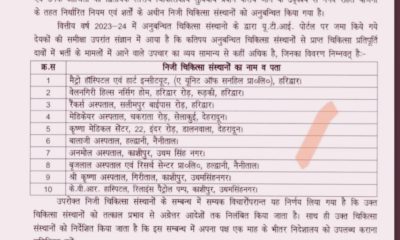

हल्द्वानी

हल्द्वानी के ब्रज लाल सहित प्रदेश के 10 हॉस्पिटल कर रहे थे भ्रष्टाचार : पकड़े गए ।।

May 5, 2024निजी हॉस्पिटलों की मनमानी हल्द्वानी – उत्तराखंड के अस्पतालों में कई बार आरोप लगते रहते हैं...